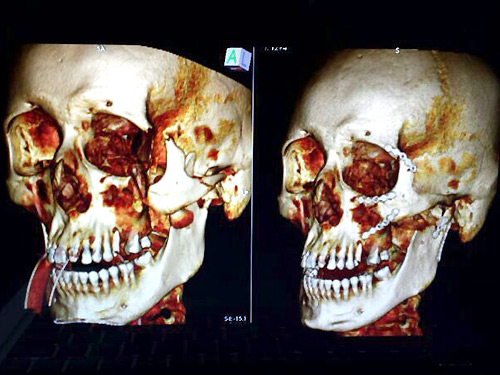

En la tomografía craneal computarizada, que aparece en tercera dimensión, se pueden apreciar los tornillos en el malar izquierdo, el maxilar izquierdo y en el arco cigomático de dicho lado.

En la tomografía craneal computarizada, que aparece en tercera dimensión, se pueden apreciar los tornillos en el malar izquierdo, el maxilar izquierdo y en el arco cigomático de dicho lado.